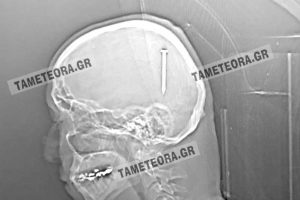

Ένα πραγματικό θαύμα έζησε πρόσφατα ένας Καλαμπακιώτης. Όπως κατέγραψε η ιστοσελίδα tameteora.gr ο άτυχος άντρας βρέθηκε ξαφνικά με ένα καρφί 5 εκ. στο κεφάλι...